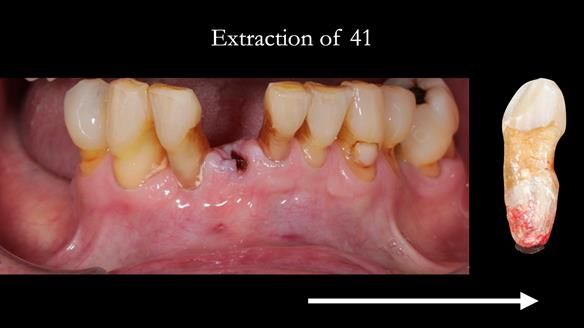

Welcome to my Newsletter 54 showing the making and fitting of dentures (a complete upper metal reinforced denture, a lower immediate partial denture and a definitive Scandinavian designed, metal based lower partial denture) for David, a 75 -year-old man. The full protocol workflow is presented including the use of dentate photographs to mimic his natural teeth.

- Missing teeth on the lower right side. This makes the upper denture tip when chewing and biting.

- The remaining lower 9 teeth had periodontal disease. Syed Abad, Specialist in Periodontics at the practice managed it.

The clinical situation and treatment process is shown in detail below. I provided the clinical work. Rowan Garstang, my dental technician, provided the technical work.